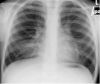

FIGURE 1

A plain chest radiograph of a patient with ataxia telangiectasia showing diffuse bibasal interstitial changes.